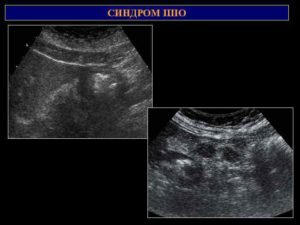

В отличие отнеизмененного желудка, когда виднаузкая периферическая часть и болееширокий эхогенный центр, при той илииной патологии с вовлечением в процессстенки желудка вышеописанные пропорциинарушаются. Анэхогенная периферическаячасть становится широкой, а эхогеннаяцентральная часть становится или кажетсяотносительно небольшой. Это состояниеобозначают как синдром поражения пологооргана (ППО).

Ультразвуковыесимптомы патологии кишечника аналогичнытаковым при патологии желудка ипредставлены синдромом поражения пологооргана, являющегося универсальным дляпоражения всех полых органовжелудочно-кишечного тракта.

Синдром пораженияполого органа (ППО) проявляется расширениемпериферического кольца кишки на томили ином протяжении за счет утолщенияее стенки, и относительным уменьшениемцентральной части кишки.

Синдром ППО выявляютпри утолщении стенки кишки вследствииразвития в ней отека, кровоизлияния,фиброза или опухоли.

При выявлениисиндрома ППО в целях дифференциальнойдиагностики проводят измерениемаксимальной толщины стенки кишки,протяженности процесса по органу,наружного диаметра кишки и величиныпросвета в зоне максимальной толщиныстенки.

Кроме вышеуказанных параметровучитывают следующие признаки: форму исимметричность пораженного участка,равномерность толщины стенки, степеньэхогенности и структуру стенки,симметричность расположения и формуцентральной части, наличие перемещениясодержимого в области центральнойчасти, состояние наружного контуракишки, подвижность при дыхании, переменеположения тела и пальпации, наличиеболезненности в области пораженногосегмента.